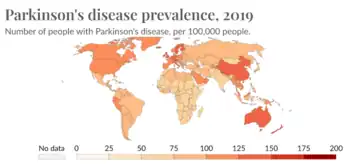

Epidemiological studies have shown lower age-related prevalence of Parkinson's disease in South Asians, with the rate of prevalence being around 52.7 per 100,000 as compared to a higher prevalence rate observed in populations with European origin, 108-257 per 100,000. Additionally, several studies have seen a higher prevalence of in women which contrasts with global data that observes a overall higher prevalence seen in men. Compared to most of the rest of the world, the South Asian countries (including India, Pakistan, Nepal, Bhutan, Maldives, Afghanistan, Sri Lanka, and Bangladesh) seem to be on the lower end of PD prevalence. However, this is not to say that PD is not of concern in these countries. Over the past couple of years, the rate of Parkinson's has gone up in South Asia meaning that it is of high importance to study this pathological disease in these populations.[1]